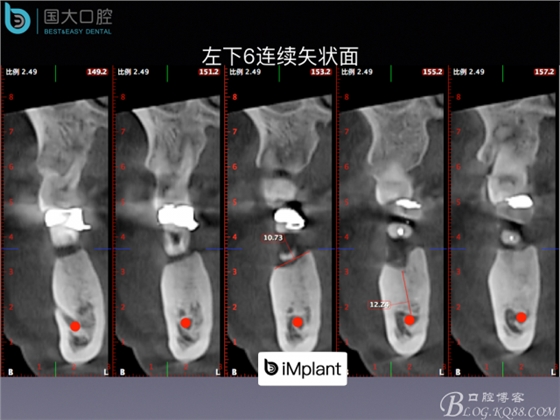

20160715154344_61331.jpeg